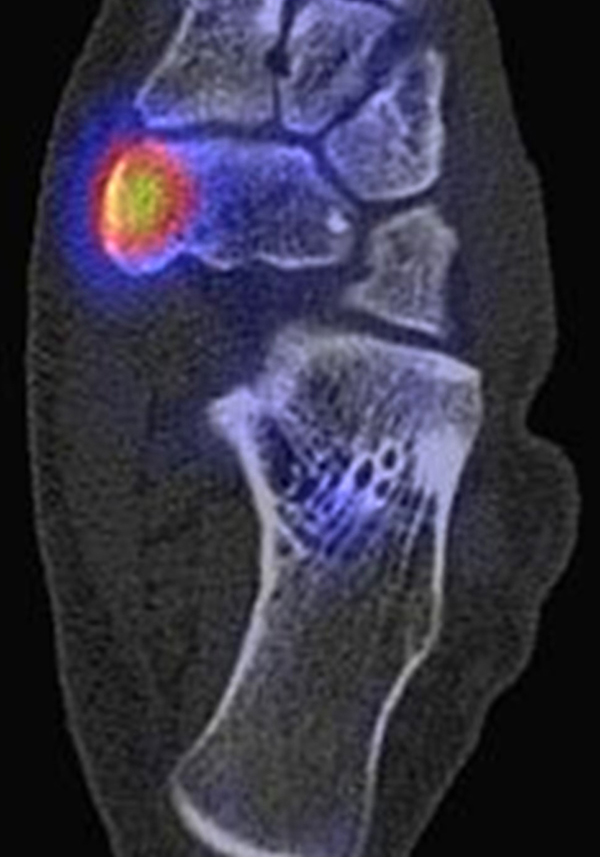

Abbildung 2.1.

Bildbeispiele symptomatische OCL

Zum Lesen der Bildbeschreibung und zur Vollansicht bitte das Bild anklicken. Bild: H. C. Rischke